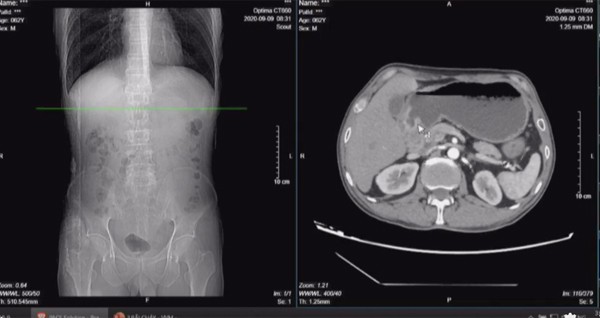

Cơ thể gầy gò, giọng nói thay đổi và hay khó thở, sặc thức ăn, khi vào viện ông Hưng được chẩn đoán mắc cùng lúc 2 ung thư.